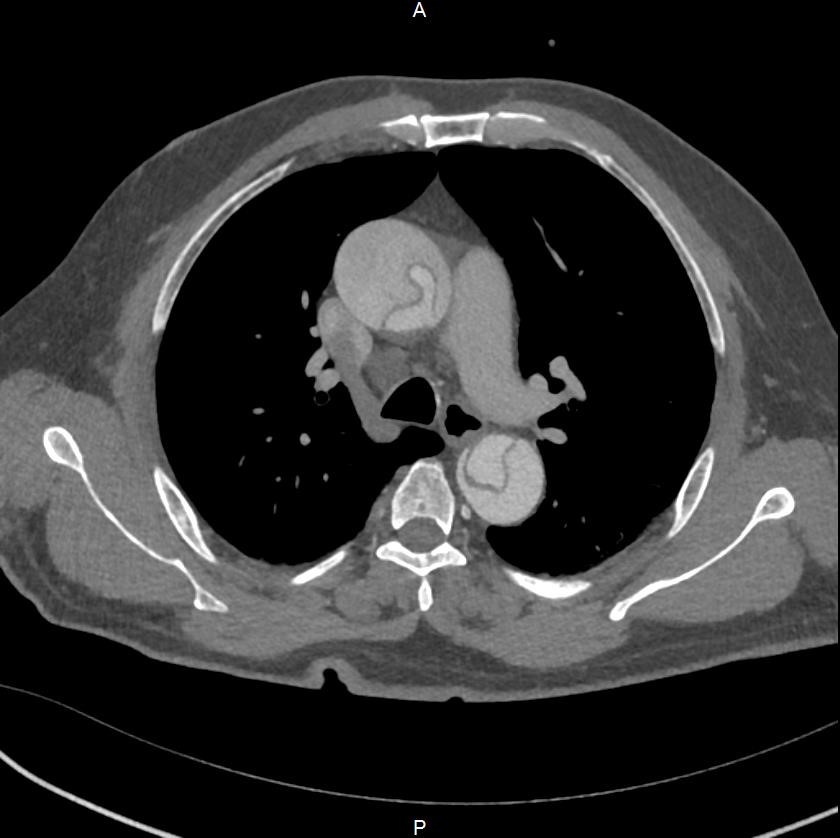

11月初的深夜,一位60岁左右的男性患者因突发胸背部剧烈疼痛被送往新华医院奉贤院区急诊。主动脉CTA检查结果显示,患者确诊为A型主动脉夹层,夹层范围从心脏根部延伸至胸、腹部及下肢,更危急的是,夹层已累及供应右侧大脑的右颈总动脉,导致血管完全闭塞,右侧大脑血供中断。

图1:典型A型主动脉夹层累及升主动脉